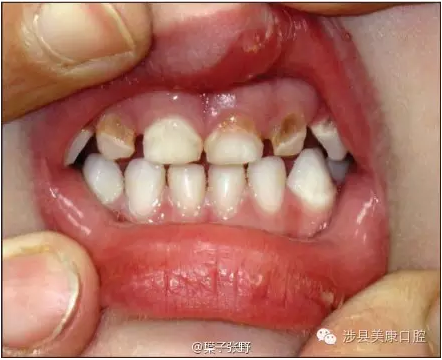

WKJ6E}Q4_)LZ3W%@CMO}L0X.png

蛀牙會(huì)疼痛,非常痛。孩子可憐死了,影響吃飯。

影響美觀,讓小朋友笑話。

造成恒牙釉質(zhì)發(fā)育不良。

引起恒牙萌出亂位。